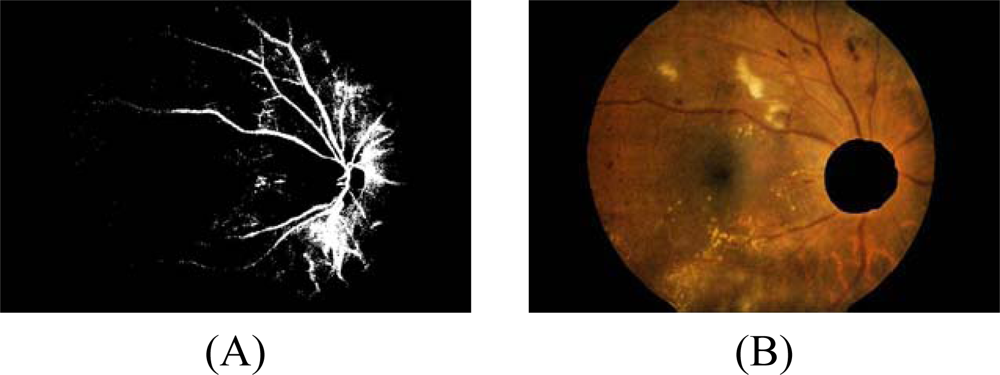

- 4.3 However, some of the resulting edge pixels from the previous step do not represent the edge of the exudates. Some of them are part of vessel’s edge and these vessel edge pixels need to be removed before proceeding to the next step. Quick and approximate blood vessel detection is achieved by using a decorrelation stretch on the Red band. The decorrelation stretching is a process used to enhance or stretch the color differences found in a color image. Contrast exaggeration is used to expand the range of intensities of highly correlated images [24, 25]. Blood vessels can be detected by thresholding this result and the detection result are shown in Fig. 2A.

- The optic disc is quickly detected by using an entropy feature on ICLAHE. The entropy is a statistic measurement of randomness that can be used to characterize the texture of the input image. The optic disc which is normally smooth appears in relatively low intensity in Entropy space. The resulting image is thresholded at an automatically selected grey level, using the Otsu algorithm [26]. Normally, the optic disc can be easily identified as the largest area. However, in some cases, such as the appearance of huge exudates in the image, there might be some areas in the image which are larger than the optic disc. Because the shape of optic disc is round, therefore the optic disc region selection process needs to be made specific to the largest one among the regions whose shapes have compactness, as calculate by Equation 7, close to one. To ensure that all the neighbouring pixels of the thresholded result are also included in the candidate region, a binary dilation operator is also applied. For this step, a flat disc-shaped structuring element with a fixed radius of 11 is used. An example result of an image with all the optic disc area masked out is shown in Figure 2B.